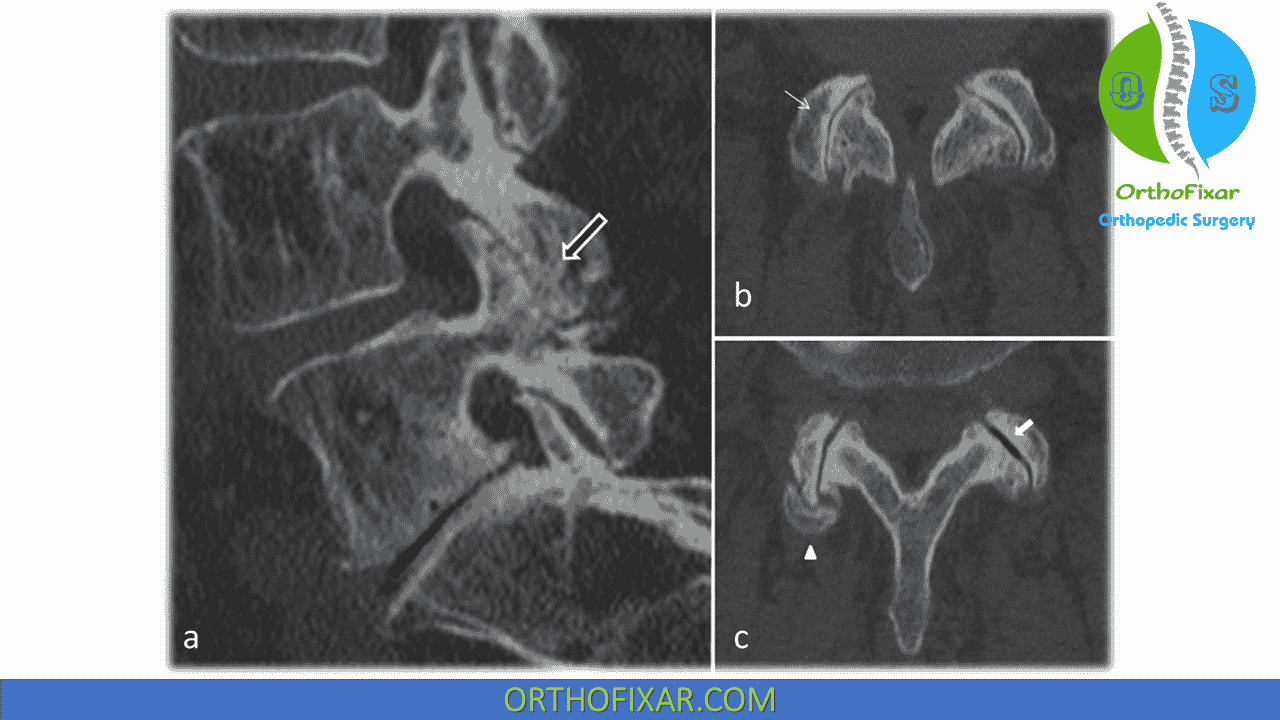

From pubs.rsna.org

Differential Diagnosis of Facet Joint Disorders RadioGraphics Facet Joint Dysfunction Icd 10 Facet joint disorders have a wide range of causes and, because of the potential for chronic back pain and disability, an accurate diagnosis is essential. Facet syndrome is an articular disorder related to the facet joints and their innervations, and produces both local and radiating pain. 55% of facet syndrome cases occur in cervical. Lumbosacral facet syndrome refers to a. Facet Joint Dysfunction Icd 10.

Differential Diagnosis of Facet Joint Disorders RadioGraphics Facet Joint Dysfunction Icd 10 55% of facet syndrome cases occur in cervical. Facet joint disorders have a wide range of causes and, because of the potential for chronic back pain and disability, an accurate diagnosis is essential. Facet joint disease, or facet syndrome, is when these joints become a source of pain. Therefore, we reviewed the latest research progress of facet joint syndrome from.. Facet Joint Dysfunction Icd 10.